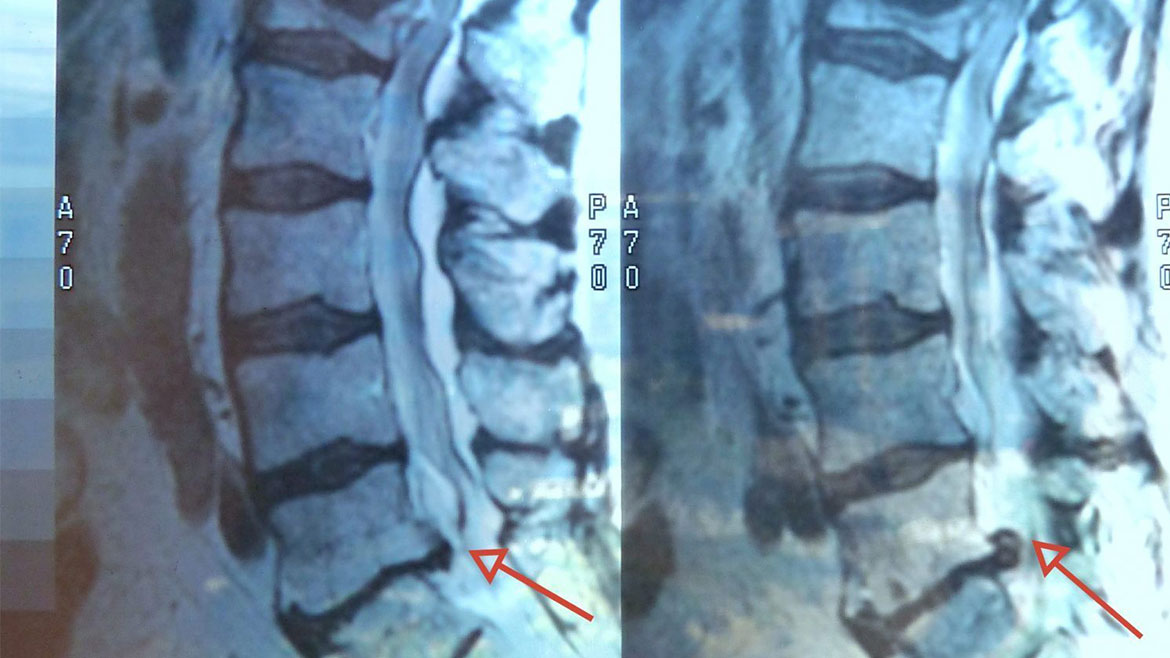

Bel Fıtığı

02

Bel bölgemizde bulunan omurgaların arasındaki kıkırdak yapının yırtılarak, omurilikten çıkan sinirleri sıkıştırmasıdır.

Bel Kayması

08

İki komşu omurganın üstteki omurganın alttaki omurgaya vertebraya göre öne doğru kayması veya yer değiştirmesidir.